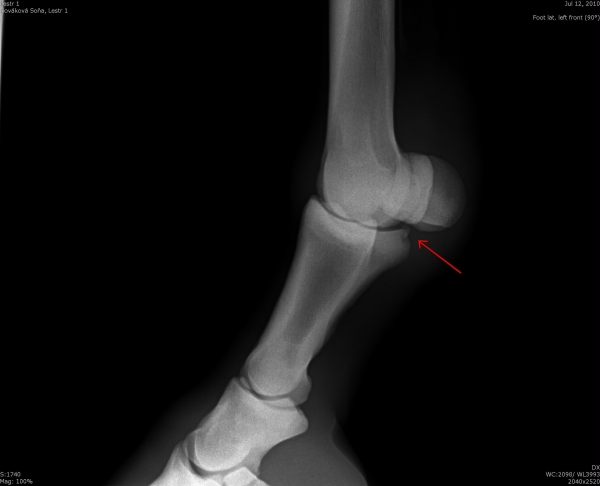

Čip ve spěnkovém kloubu na pánevní končetině

Ankylóza spěnkovýho kloubu

rentgenologické vyšetření

ohebové zkoušky

ultrasonografické vyšetření klisny